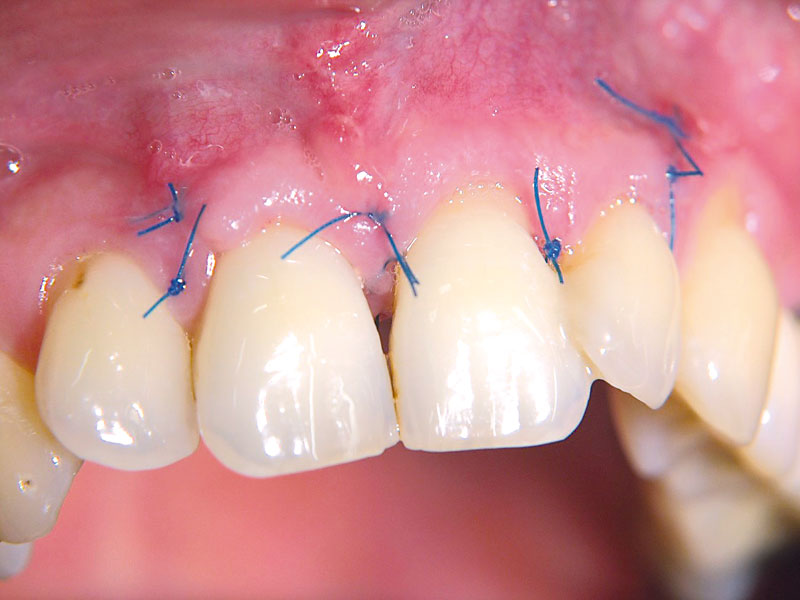

08/11 - Suturing of the membrane.Non-contained intrabony defect treated using cerabone®, collprotect® membrane and Straumann® Emdogain® - Dr. T. Schwaar (2)

09/11 - Flap closure.Non-contained intrabony defect treated using cerabone®, collprotect® membrane and Straumann® Emdogain® - Dr. T. Schwaar (2)